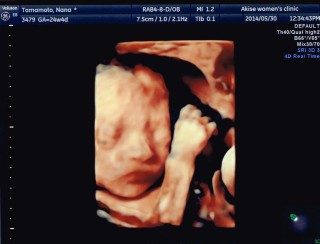

781グラムの元気な女の子です!心臓の動き、動脈の全てが正常。先生に「顔が整ってますね~可愛い」と連発されました☆嬉しいものですね。 私の体重が仕事の多忙さからか、1.1キロ減っており、この時期には珍しいとの事。糖も足りないみたいだし、しっかり頂きます。 とにかく、元気な子で良かった。正常位で胎盤も良い位置についているとの事。分娩までに、更に体力をつけるぞ!!